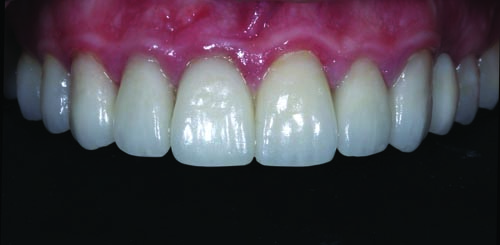

Fig. 33: Close-up retracted postoperative view of the definitive maxillary restorations, which included IPS E.max onlays, crowns and veneers.